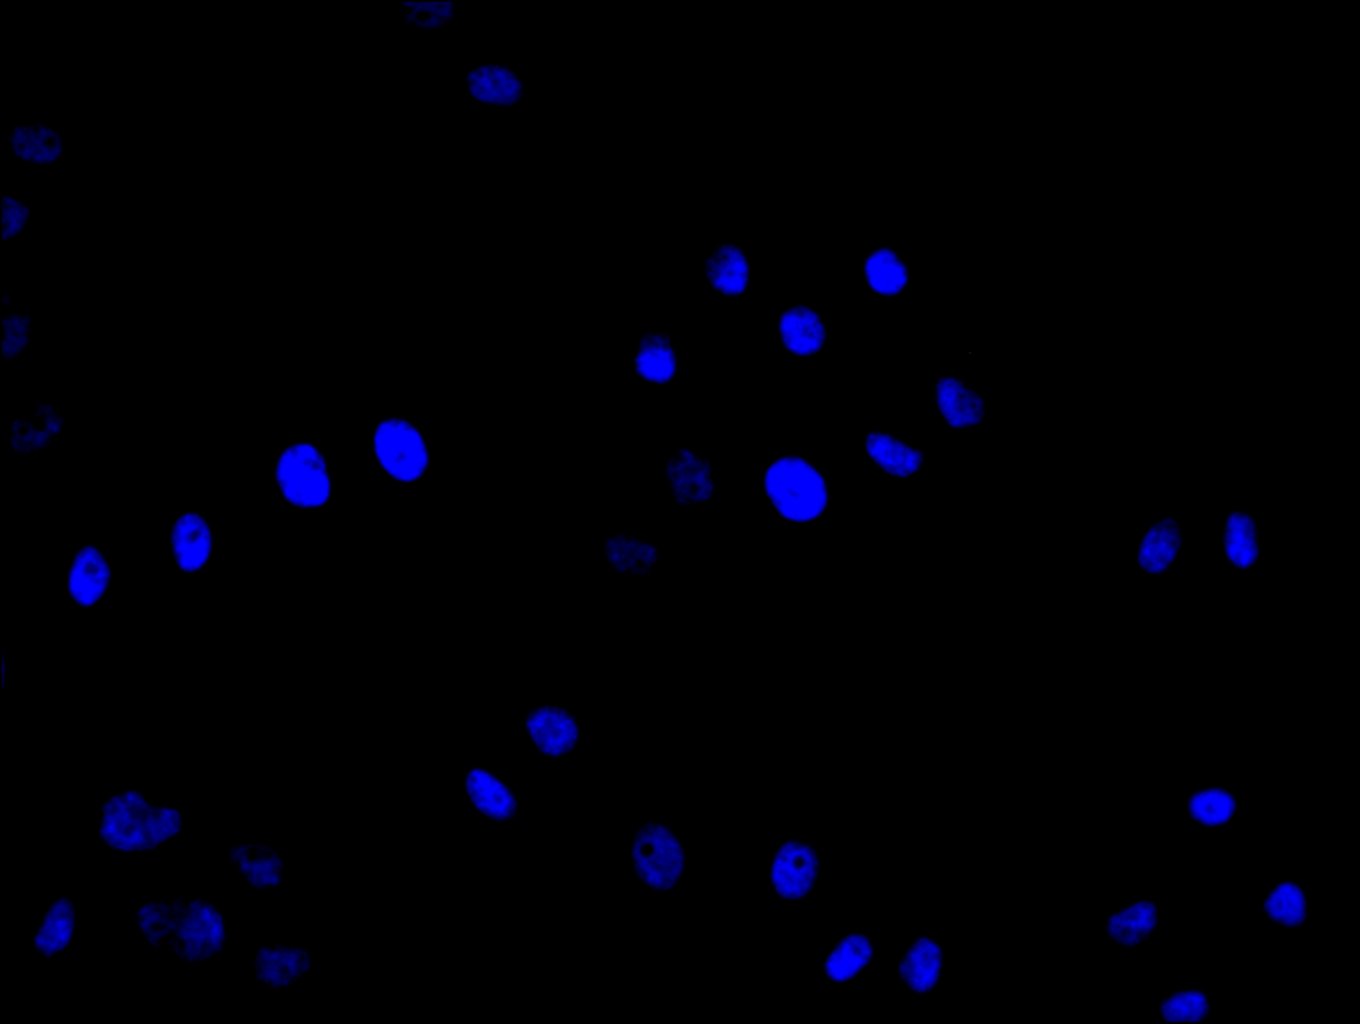

Immunofluorescence staining of Hela cell with CSB-PA751020LA01HU at 1:30, counter-stained with DAPI. The cells were fixed in 4% formaldehyde and blocked in 10% normal Goat Serum. The cells were then incubated with the antibody overnight at 4C. The secondary antibody was Alexa Fluor 488-congugated AffiniPure Goat Anti-Rabbit IgG(H+L).

Immunofluorescence staining of Hela cell with 5% goat serum, counter-stained with DAPI. The cells were fixed in 4% formaldehyde and blocked in 10% normal Goat Serum. The cells were then incubated with the antibody overnight at 4C. The secondary antibody was Alexa Fluor 488-congugated AffiniPure Goat Anti-Rabbit IgG(H+L).